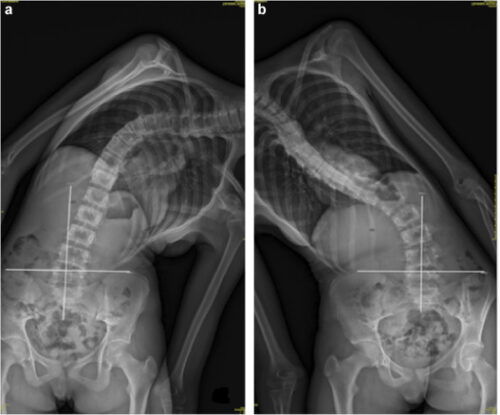

2. طريقة الانحناء الجانبي أثناء الاستلقاء: يطلب من المريض الاستلقاء والانحناء إلى الجانبين.

1. الأفضل للانحناءات المتوسطة (40°–65°).

• سهلة الاستخدام ولا تسبب ألمًا.

1. الاستلقاء مع الانحناء الجانبي للجزء الأسفل من الظهر (Supine Lateral Bending):

• مناسبة لتقييم الانحناءات في منتصف وأسفل الظهر.

• توفر صورة واضحة عن مرونة الجزء السفلي من العمود الفقري.